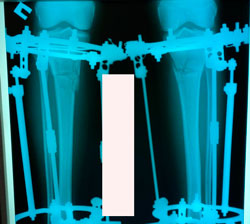

Исходник - 30 лет.

Дата операции - 25.12.2020

Диагноз: варусная деформация + Ротация с обеих сторон.

на фиксации